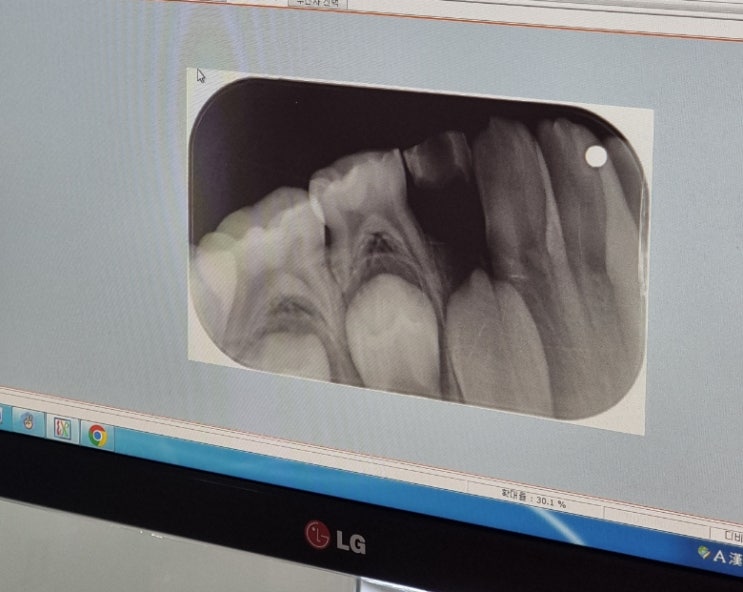

초등 치아에 구멍 영구치 뿌리 흡수 예방교정 상담 후기

2~3개월 전, 우리 아이 치아에 핑크색으로 콕 찍은 듯한 점? 붉은색 반점?이 생겼었어요 처음에는 사인펜이...